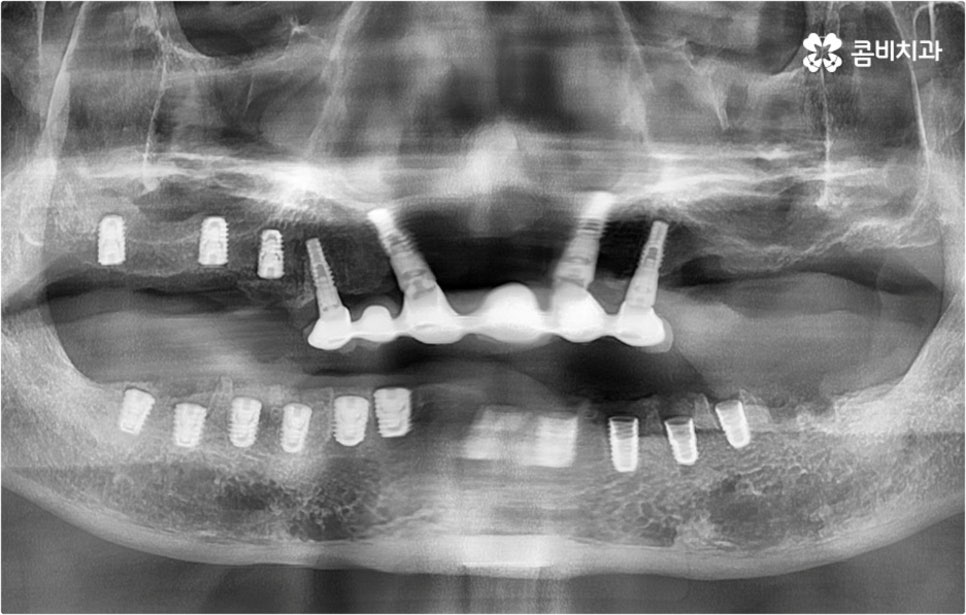

아무 것도 없는 상태에서 제대로 저작 기능을 발휘할 수 있도록 다시 구강 내부를 재현하는 전악임플란트 는 굉장히 고난도에 속하는 치료이기 때문에 충분한 임상 경험을 가지고 있는 숙련된 의료진과 함께 하실 필요가 있어요. 전악임플란트 방식이 빠진 영구치 자리마다 다 임플란트를 식립하는 것이 아니라, 상하악 각각에 8~12개 정도로 필요한 최소한의 인공 치근을 심고 그 사이 사이는 브릿지 방식으로 보철물을 연결하는 것이기 때문에 저작력을 골고루 분담하여 안정적인 지속성을 높일 수 있도록 환자 개개인의 상태에 맞게 인공 치근의 위치, 각도, 간격, 심는 깊이 등을 세밀하게 설정하여 교합을 제대로 맞출 수 있는 시술자의 뛰어난 기술력과 풍부한 노하우가 요구되는 거예요.

또한 이를 위해서 치아 주변 조직과의 거리나 잇몸뼈 높이, 밀도 등을 정확하게 파악할 수 있도록 도와주는 3D CT와 같은 정밀 진단 장비를 갖추고 환자분들의 상황에 맞는 계획을 세워 무리하지 않게 진행할 수 있는 체계적인 시스템을 운용하는 치과에서 임플란트 시술을 받으실 필요가 있어요. 만약 치과내 자체 기공소를 갖추고 있다면 보철물 제작에 대한 피드백이 보다 빠르게 전달, 반영될 수 있어 환자분들이 이용하시기에 좀 더 편안하실 거예요.

임플란트 수술 후 발생할 수 있는 혹시모를 부작용 중 가장 대표적인 것은 주변 잇몸에 염증이 생기는 거예요. 임플란트 치아는 구조상 자연 치아와 다르게 자연스럽게 움직이면서 충격을 흡수하는 치주 인대가 없는 만큼 갑작스럽게 큰 힘이 가해질 수 있는 너무 딱딱한 음식을 씹으면 잇몸에 부담이 가서 피가 나거나 부어 오를 수 있으며, 주변 위생을 청결하게 유지하지 않으면 세균이 증식하여 염증이 생길 수 있으니 항상 잇몸 건강 상태를 양호하게 관리하는데 신경쓰실 필요가 있어요.